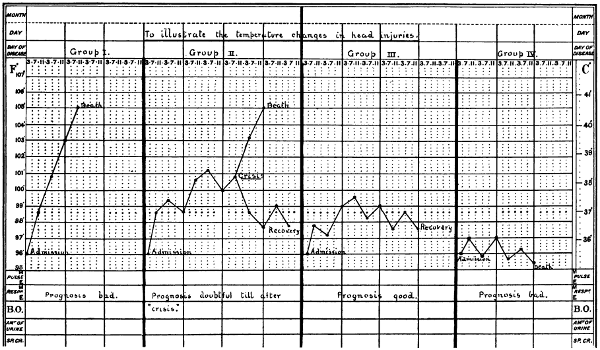

| 44. A temperature chart illustrating the changes in temperature observed in head-injuries | 117 |